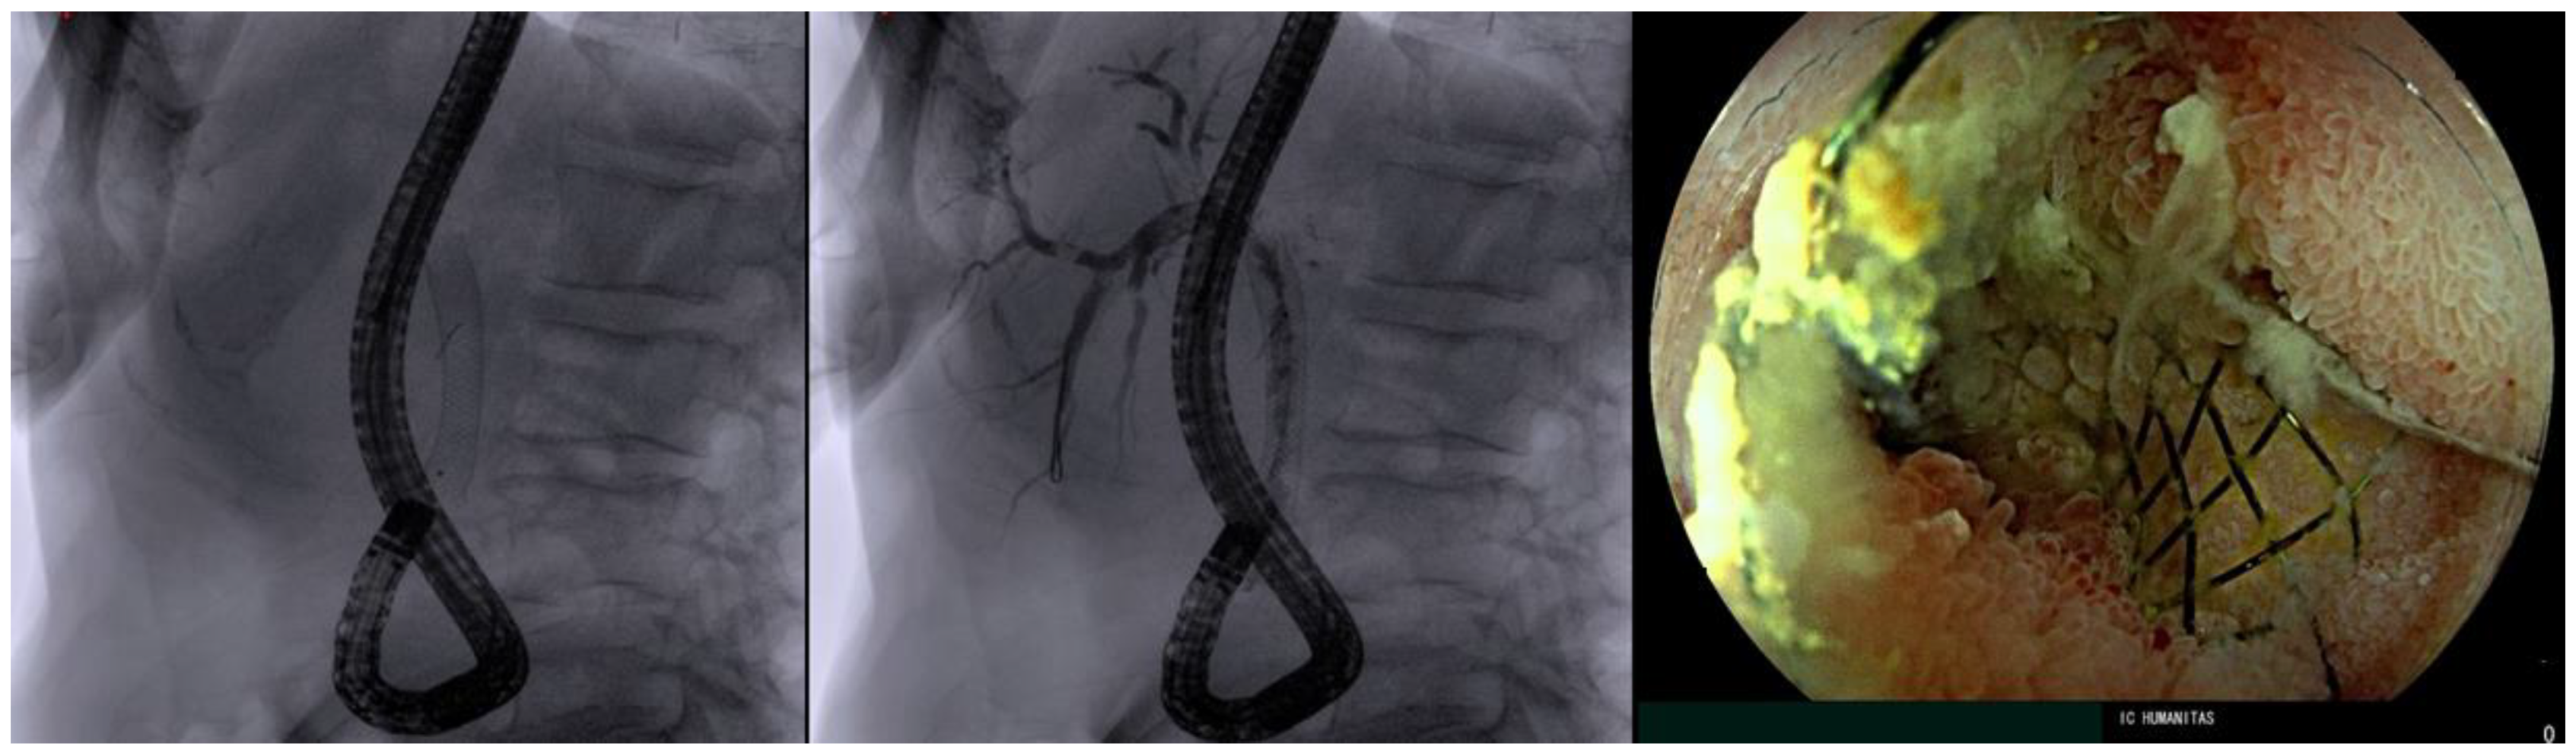

- Fugazza, A.; Anderloni, A.; Paduano, D.; Badalamenti, M.; Maselli, R.; Carrara, S.; Gabbiadini, R.; Colombo, M.; Spadaccini, M.; Cappello, A.; et al. Underwater cap-assisted endoscopic retrograde cholangiopancreatography in patients with surgically altered anatomy: A pilot study. Endoscopy 2021, 53, 927–931. [Google Scholar] [CrossRef]